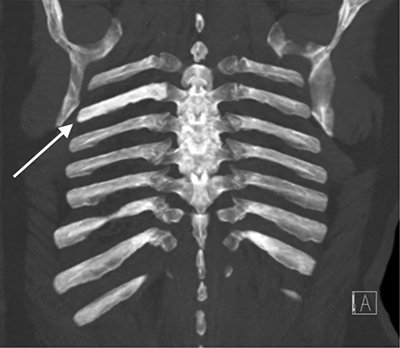

Figure 2B

CT thorax coronal MIP images.